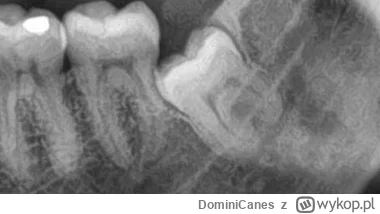

Masz zęba:

1 całkiem zatrzymanego

2 częściowo zatrzymanego

3 rosnącego normalnie ?